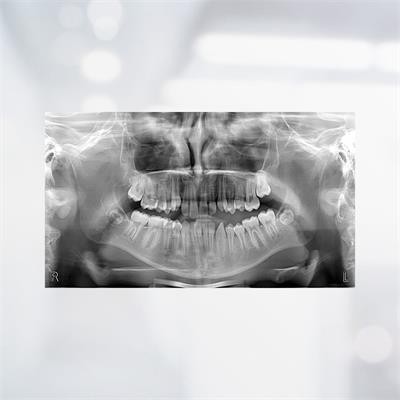

XDI-200 & 250 (Stellaris 2D) is the most innovative panoramic of the Xline portfolio. Based on the well-known and reliable platform, it offers a brilliant new image quality, thanks to the new dynamic image focusing technique.

XDI-200 (Stellaris 2D) covers a variety of diagnostics in 2Dand Ceph with one shot ceph images and programs for panoramic examinations.

High Definition and ECO Program

Adult and, more importantly, child programs are crucial for ECO low dose examinations, allowing high diagnostic image quality for both overview and demanding diagnostic tasks.